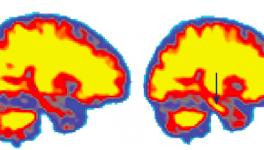

Regular, Good Quality Sleep Could Be a Way to Prevent Alzheimer’s